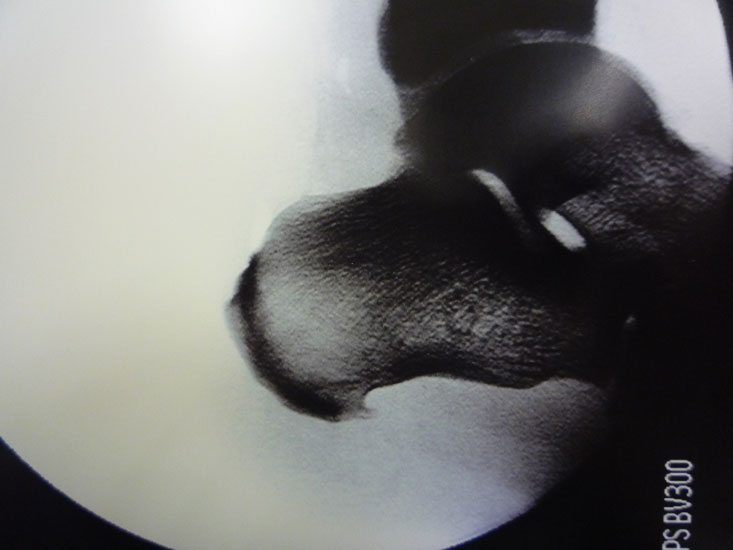

Abbildung 10, Video 5

Das OP-Ergebnis wird mit dem Bildwandler dokumentiert. Hierbei ist es wichtig, auch mediale und laterale Schrägaufnahmen anzufertigen, um keine weit posteromedial oder -lateral gelegenen Exostosenreste zu übersehen (Calcaneus seitlich, sowie 45° Innen- und Außenrotation). Ergänzend zu Röntgenaufnahme sollte der mediale und laterale Calcaneus abgetastet werden, um das Risiko einer belassenen Knochenkante möglichst gering zu halten. Der Hautverschluss erfolgt in Einzelknopftechnik, eine Ruhigstellung ist nicht erforderlich.

Abbildung 11-12

Prä- und postoperatives Röntgenbild.